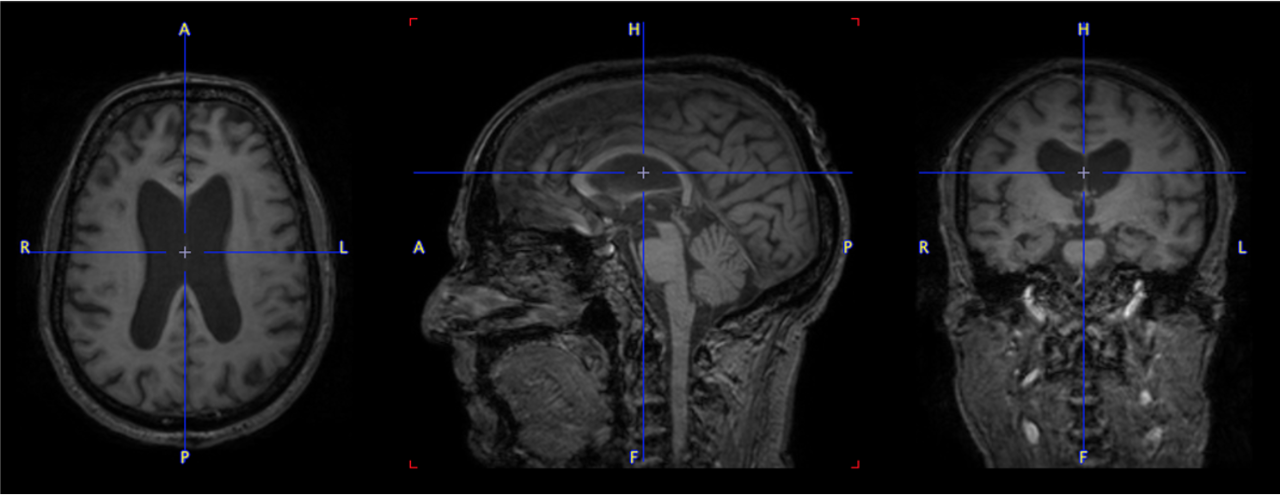

pmod’s tools provide comprehensive workflows for post-processing and quantification of imaging data for fundamental oncology research, development of radiotracers and theranostics, and in clinical research studies. Imaging scientists can trust pmod to reproducibly read their data, interpret the meta-data/units and help users calculate statistics such as SUV for their studies and publications.

• Multimodality segmentation tools – comprehensive semi-automated and manual tools for precision and reproducibility